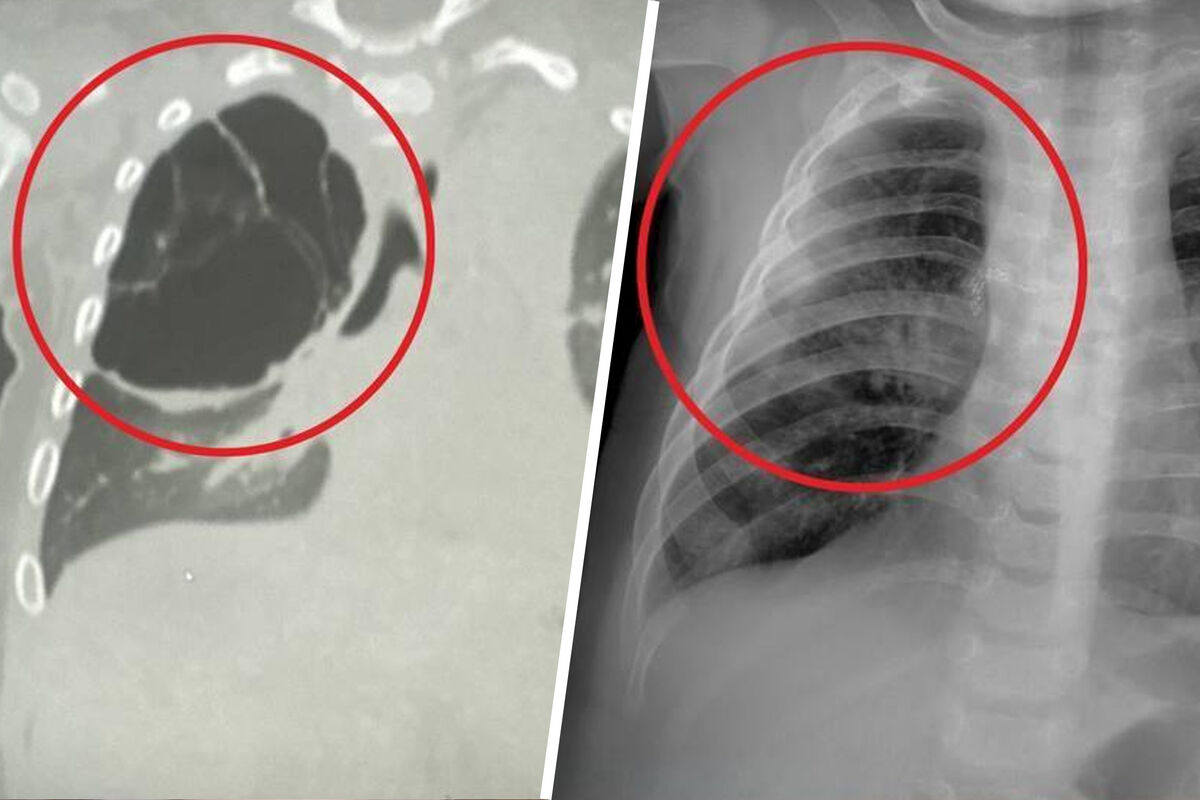

Как рассказали медики, образование было обнаружено во время воспалительного процесса, вызванного острой респираторной вирусной инфекцией. Киста занимала большую часть правого легкого ребенка и не давала ему полноценно развиваться. Врачи приняли решение удалить образование.

«Детские хирурги провели торакоскопическую операцию: без разреза аккуратно удалили кисту вместе с пораженной частью верхней доли правого легкого», — поделились в минздраве.

Операция длилась около часа и завершилась благополучно. Размер кисты составил около 15 сантиметров.